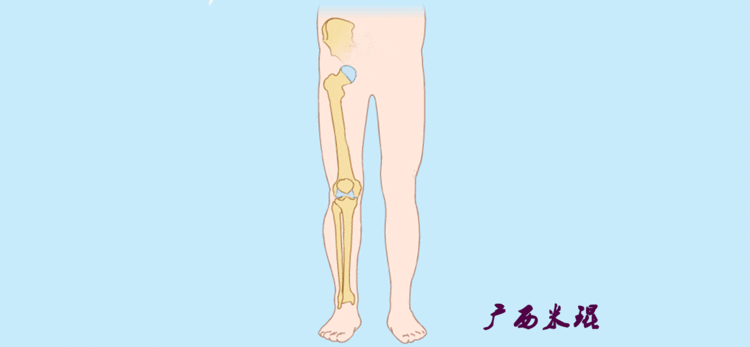

2、画出下肢的轴线确定髋关节、膝关节、踝关节的中心点后,我们才能了解下肢的几个轴线。(1)解剖轴股骨和胫骨的骨干中线为解剖轴,股骨解剖轴和胫骨解剖轴的夹角正常值为174°±1°。

(2)机械轴机械轴是连接近端和远端关节中心点的直线。

机械轴要分前后位及侧位,站立前后位(也就是冠状面)股骨头中心与踝关节中心的连线通过膝关节中心,这是下肢的机械轴线,也就是下肢力线,常说Mikulicz线。冠状面的力线评估在临床工作中最常用、最基础、最重要。

(3)垂直轴也就是下肢的负重轴,它是身体的纵轴线,与地面垂直,由于双髋比双踝的距离宽,所以垂直轴与下肢力线(机械轴)存在3°的外翻。